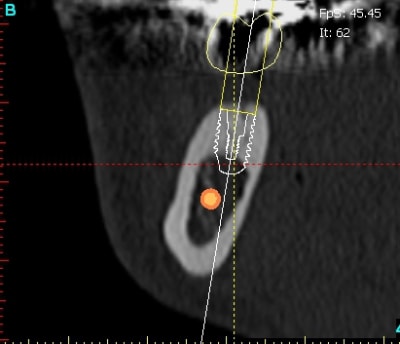

pour candide candida, et pour montrer que je ne suis pas anti scan,

patiente adressée, pano correct, mais à l'examen endo-buccal un petit doute sur la largeur d'os: scanner et bien que non indispensable, utile quand même, car visu de la corticale "sympa"

tabac, 10/15 par jour, 42ans.

désirant faire une pose de deux implants, diam 3.4 mini voir 4 si possible le doute était pour 46 et le scan me montre une épaisseur qui va nécessiter une expansion (what else) et surtout une corticale du type qui ne se plie pas facilement.

le post c'est surtout pour montrer que je ne suis pas pour les scans systématique,(comme certains "experts") mais que c'est un bel outil et que si il y a interrogation, je n'hésite pas à en demander.